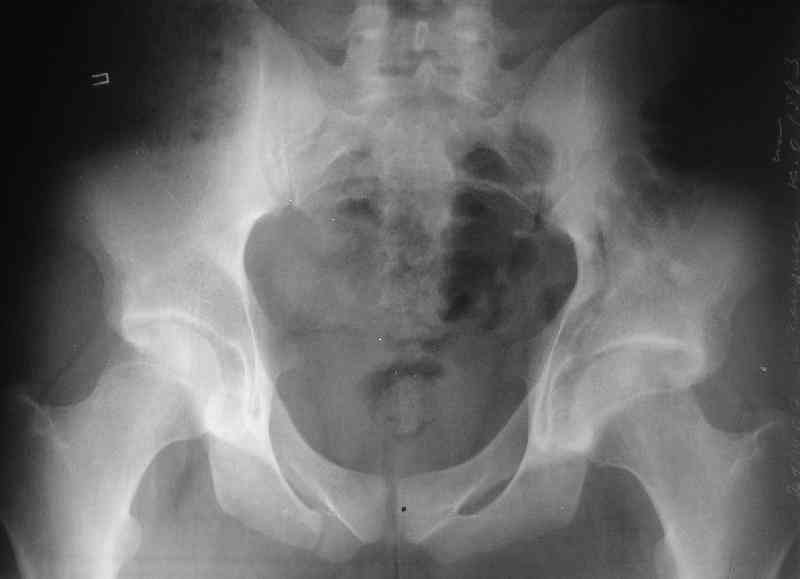

Нелеченный перелом вертлужной впадины

Мужчина 33 лет получил травму в шахте (придавило вагонеткой) 6 недель назад. Изолированное повреждение вертлужной впадины.

В местной больнице отлежал несколько недель на вытяжении. После выписки амбулатрный травматолог направил в институт. На сегодня, похоже, уже имеется неправиильное сращение. См. картинки.

Вопрос - что делать сейчас? Оставить как есть или идти на открытое восстановление? Если последнее, то какой доступ, репозиционные манипуляции и фиксацию тут можно посоветовать? Заранее спасибо.

Dear all, A male 23 y.o. injured 6 weeks ago - mine trauma, impacted by a carriage. Isolated injury of the acetabulum. At the initial hosptial was on bed traction some weeks. After discharge visited anotheк orthopaedic surgeon who referred him to our unit. To date looks like a malunion. Images attached. The question is about what to do now - either leave it as is or perform open reduction? If the latter what approach, reduction manoeuvres and fixation would you advice? Thx in advance!